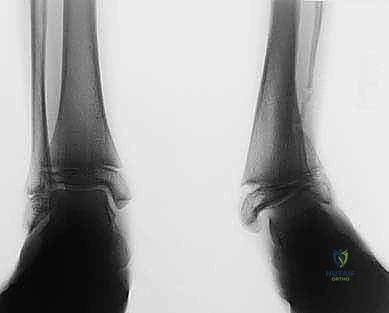

1. التخطيط الجراحي الدقيق (Pre-operative Planning)

يتم إجراء صور أشعة سينية خاصة (طويلة للساق بالكامل أثناء الوقوف) وأشعة مقطعية (CT Scan) ثلاثية الأبعاد. يقوم الدكتور محمد هطيف باستخدام برامج حاسوبية متقدمة لحساب الزاوية الدقيقة للتشوه، وتحديد حجم "الوتد العظمي" (Bone Wedge) الذي يجب إزالته أو إضافته لإصلاح المحور.

الحالة الأولى: تصحيح تشوه ما بعد كسر قديم

مريض يبلغ من العمر 42 عاماً، تعرض لكسر في الساق قبل 5 سنوات التئم بشكل خاطئ، مما أدى إلى تقوس شديد للداخل (Varus) وألم مستمر يمنعه من العمل. بعد تقييم دقيق من قبل الأستاذ الدكتور محمد هطيف، تم إجراء جراحة قطع عظم الساق فوق الكاحل بتقنية الوتد المفتوح. بعد 4 أشهر من الجراحة والتأهيل، عاد المريض لعمله الميداني بمحور ساق مستقيم تماماً وبدون أي ألم.

الحالة الثانية: إنقاذ كاحل شابة من الخشونة المبكرة

شابة تبلغ من العمر 28 عاماً، تعاني من تشوه خلقي أدى إلى تركز الوزن على الجانب الخارجي للكاحل، وبدايات تآكل غضروفي. كانت مهددة بدمج الكاحل في سن مبكرة. أجرى لها الدكتور هطيف الجراحة ببراعة، مما أعاد توزيع الوزن بشكل مثالي، وأنقذ مفصلها الطبيعي، وعادت لممارسة حياتها الطبيعية بثقة عالية.